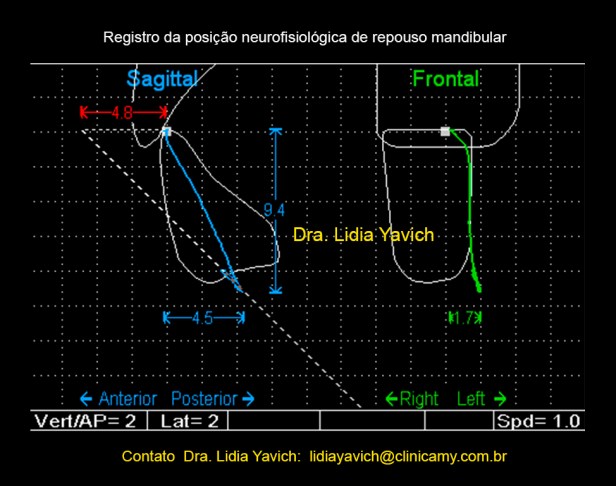

O paciente apresenta um espaço livre patológico de 9,4 mm e uma retrusão de 4,8 mm.

O paciente apresenta um espaço livre patológico de 9,4 mm e uma retrusão de 4,8 mm.

Com os dados obtidos após a desprogramação eletrônica mandibular e SEMPRE COM A INFORMAÇÃO OBTIDA NAS IMAGENS CONSTRUÍMOS o DIO (Dispositivo Intraoral) em posição neuromuscular fisiológica.